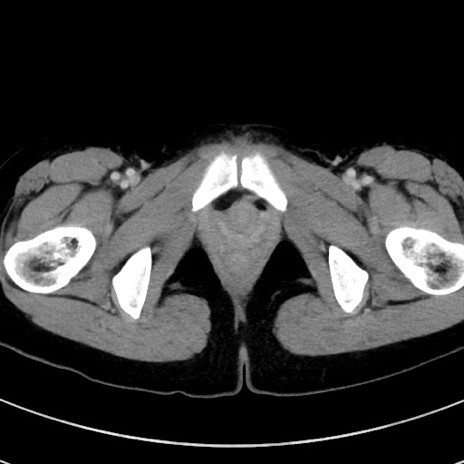

症例17(横断像)

【症例】20歳代女性

【主訴】嘔吐、下腹部痛

【現病歴】昨日夕食後に嘔吐し下腹部痛が出現。本日になっても嘔吐持続し改善しないため来院。

【身体所見】意識清明、BT 37.2℃、BP 108/67mmHg、腹部:平坦、やや硬、下腹部正中から右にかけて圧痛あり、反跳痛軽度あり、tapping pain(+)。

【データ】WBC 13600、CRP 14.94